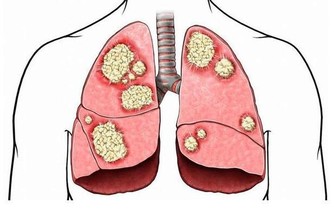

肝膽開始回血,把有毒的血過濾掉,產生新鮮的血液,到一百歲也沒有膽結石,也沒有肝炎、囊腫一類的病。

如果你天天熬夜到 1 點多,肝回不了血,有毒的血排不掉,新鮮的血生不成,膽又無法換膽汁,

所以這些人容易得膽結石、囊腫、大三陽、小三陽各種病癥。

在歐洲地區,平均四個人就有一個肝炎攜帶者,這就叫不懂規則。